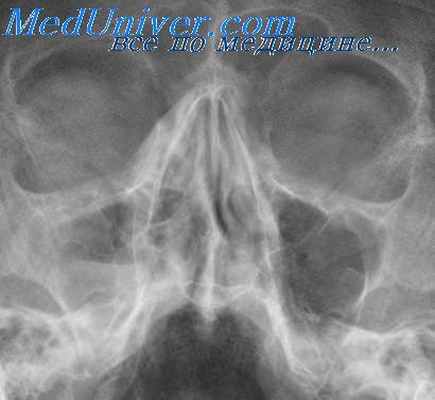

Чаще встречающаяся катаральная форма острого гайморита ведет к отеку слизистой оболочки и значительному увеличению ее толщины, что находит свое выражение в характерных рентгенологических симптомах. На типичной рентгенограмме в подбородочно-носовой проекции при наклонном положении головы больного обнаруживается незначительное понижение воздушности пазухи и характерное краевое затемнение, обычно одинаковой ширины на всем протяжении, с резкими контурами.

Такое краевое затемнение обусловлено отечной слизистой оболочкой. Таким образом, до того момента, пока существует центральное просветление пазух, т. е. полость, не занятая отечной тканью, диагноз катаральной формы острого гайморита может быть установлен рентгенологически.

При диагностике крайне важно знать, как выглядит гайморит на рентгеновском снимке. При этом методе обследования не видны мягкие ткани, зато хорошо визуализированы костные структуры. Если на снимке оттенок придаточных пазух носа и глазниц идентичен, то воспаления нет. Если же есть гнойное содержимое, то визуально оно выглядит как большие затемненные участки.

При отсутствии патологических изменений и отклонений, снимок покажет следующую информацию:

- Нос в виде треугольника светлого оттенка, посередине которого расположена перегородка.

- Сбоку от полости носа располагаются верхнечелюстные пазухи в виде треугольных просветлений с не размытыми границами.

- Симметричное расположение носовых ходов с обеих сторон от носовой полости.

- Лобные пазухи расположены над глазницами. На снимке они виды как просветления различной величины.